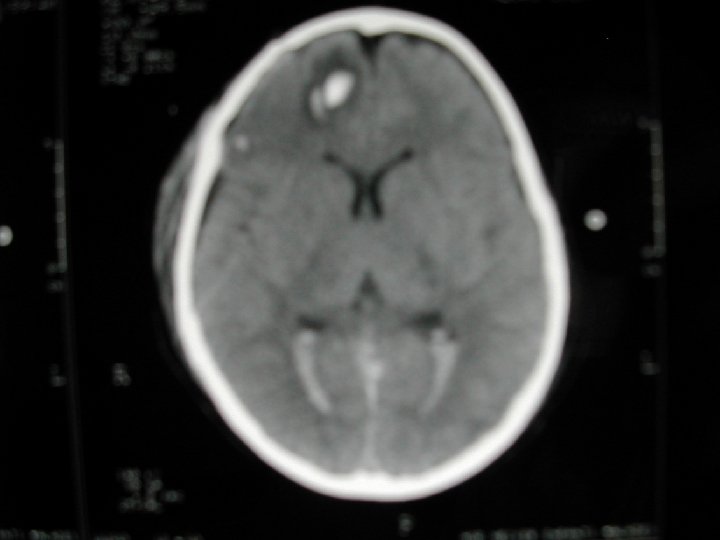

Lésions cranio-encéphaliques • Extrêmement fréquentes: 80% des patients • Hématomes intra-crâniens rares (5%) • Lésions oedèmateuses (60 -80%) • Lésions axonales diffuses les fractures ne préjugent pas de l'importance des lésions Attention: scalp = hypovolémie Traitement = Neuro-réanimation, pas Neuro-chirurgie

Lésions primaires • • • Plaies du scalp, fractures Embarrures, plaies crâniocérébrales Hématomes intracrâniens Lésions axonales diffuses HSD, HED

Hématomes extra-cérébraux • HSD sans lésion secondaire associée • HED avec engagement et œdème diffus

Lésions diffuses

Lésions secondaires • Œdème cérébral diffus • Brain swelling • Ischémie lésionnelle

Œdème diffus et ischémie étendue